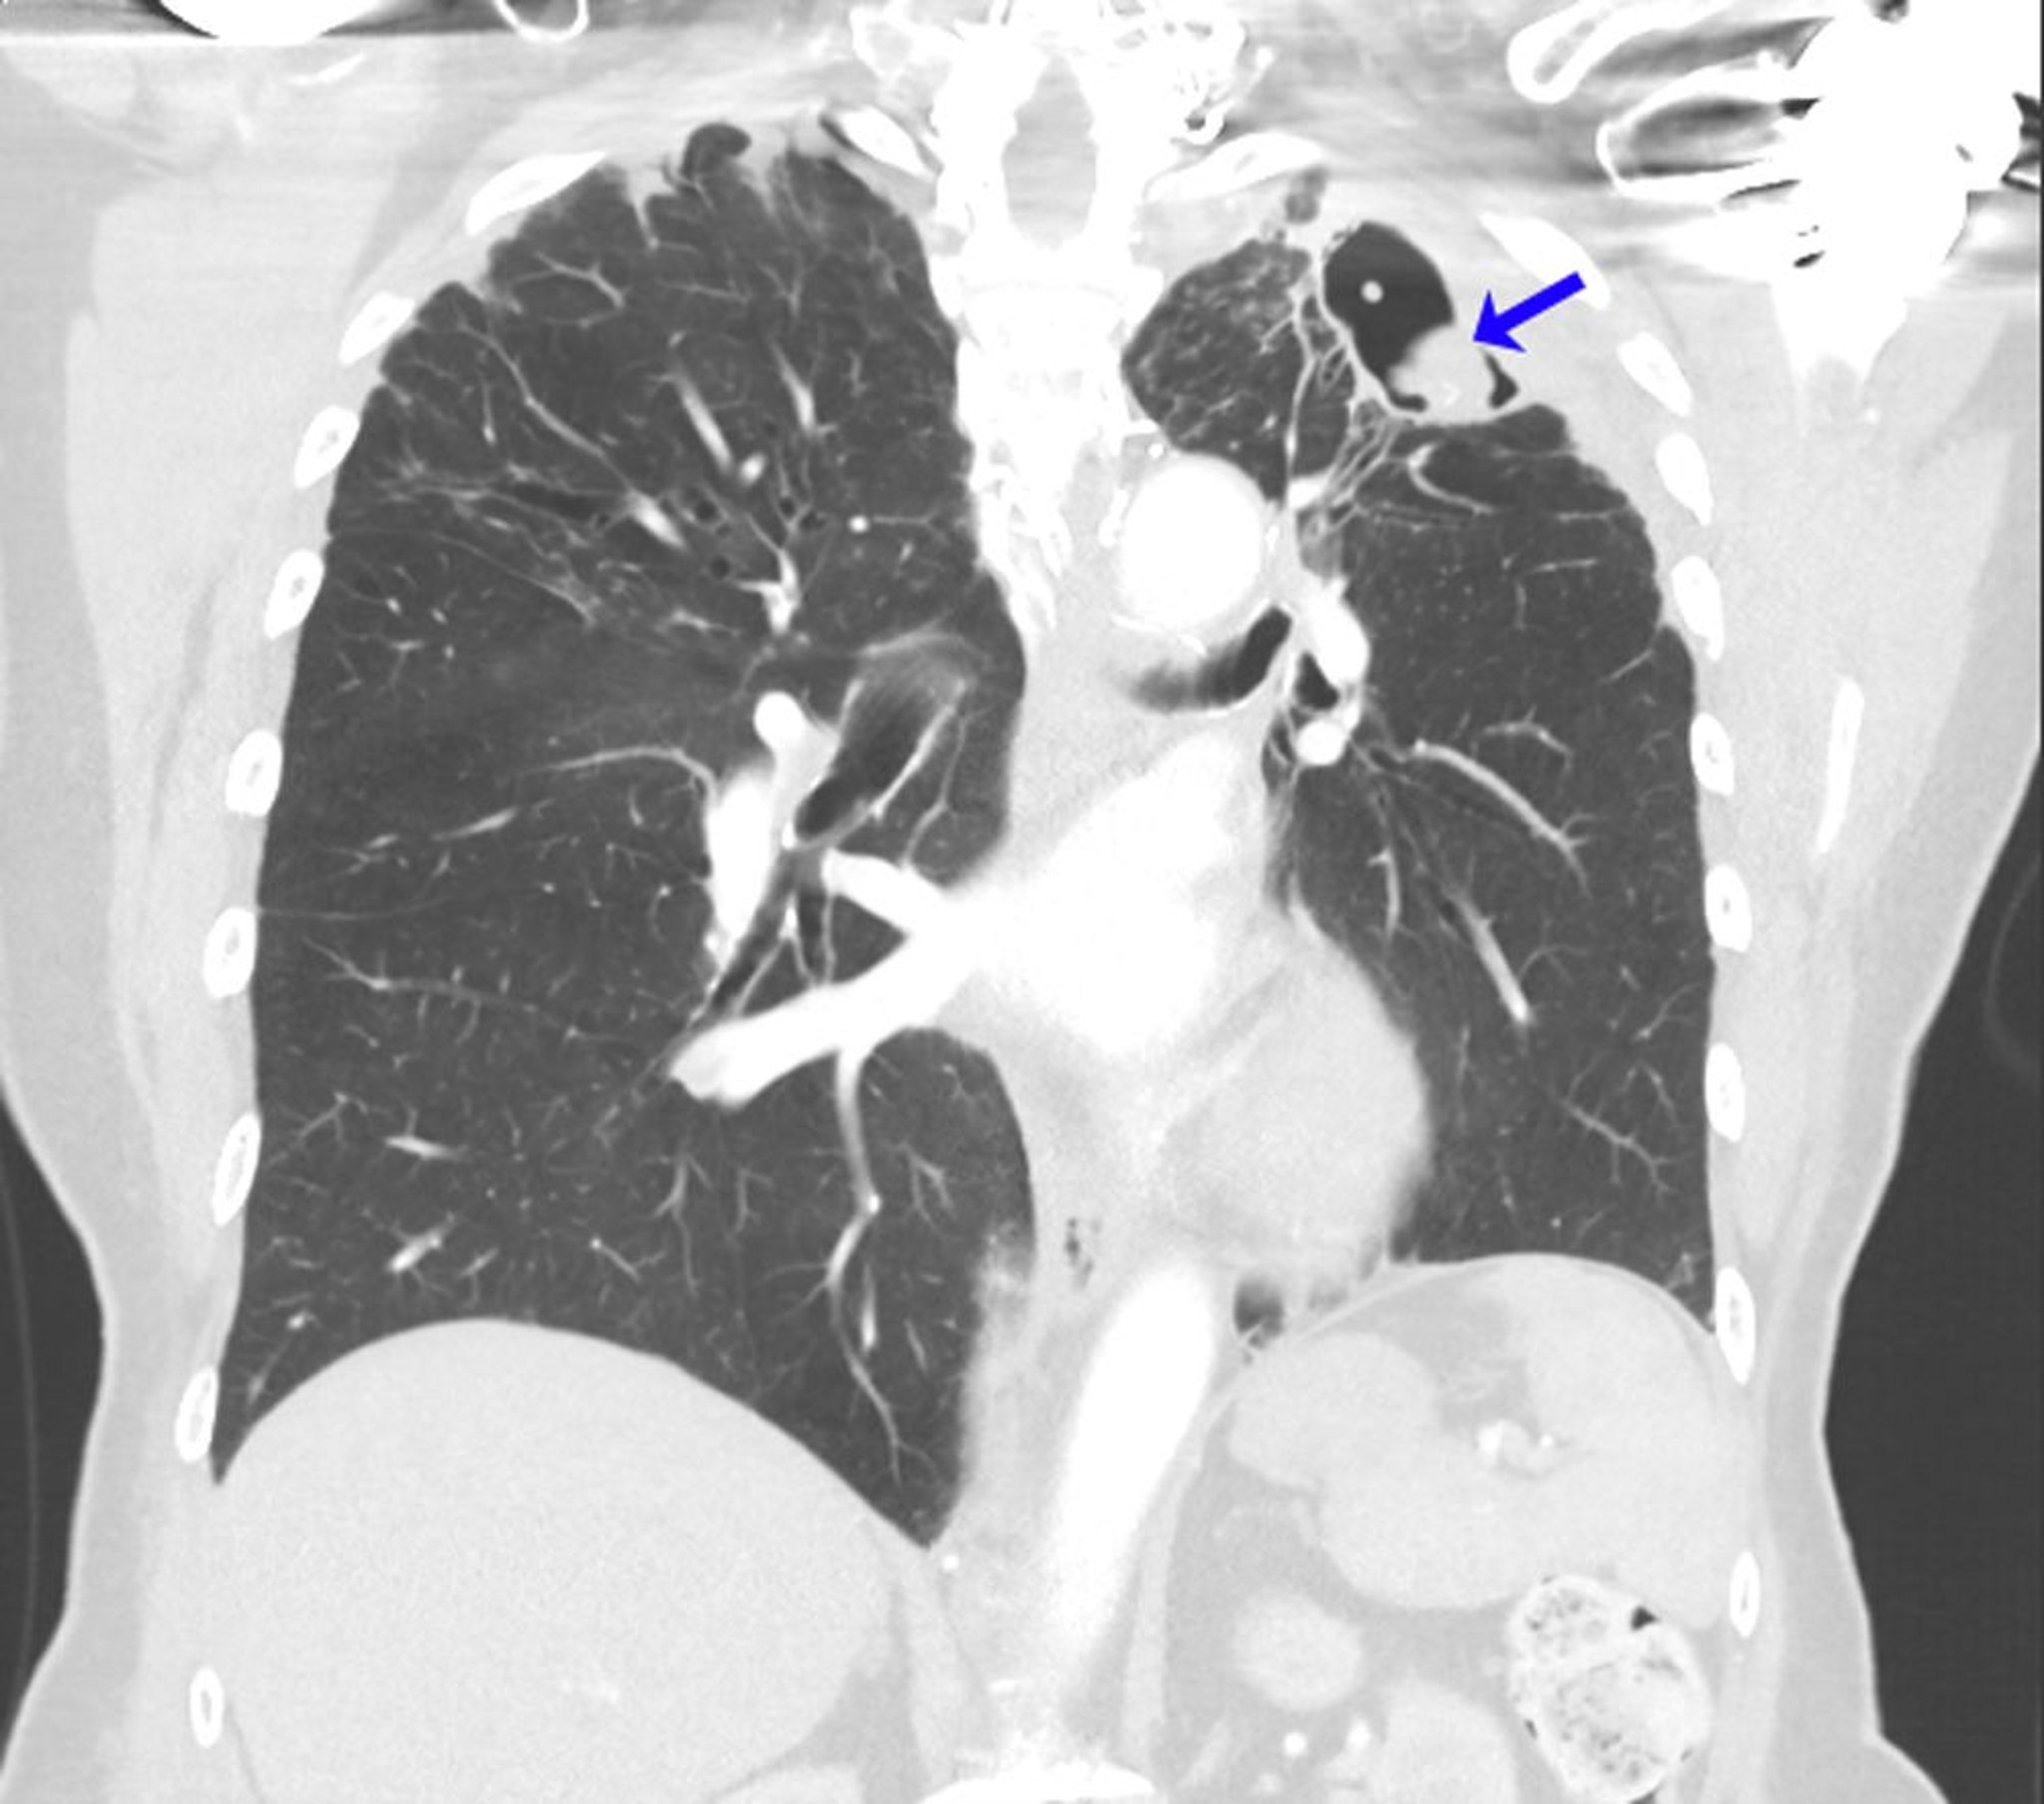

Aspergillome récidivant

Cette TDM montre les poumons d'un sujet qui a des antécédents d'aspergillose bronchopulmonaire allergique dans un contexte d'asthme. Après une lobectomie supérieure gauche pour aspergillome, un mycétome récurrent s'est développé à l'apex du poumon gauche (flèche).

Image courtoisie de Paschalis Vergidis, MD, MSc.